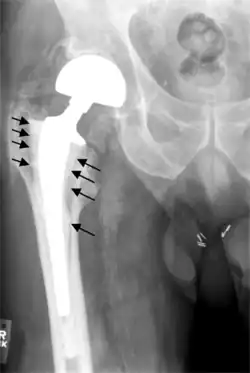

Hip prosthesis displaying aseptic loosening (arrows)

On radiography, it is normal to see thin radiolucent areas of less than 2 mm around hip prosthesis components, or between a cement mantle and bone. These may indicate loosening of the prosthesis if they are new or changing, while areas greater than 2 mm may be harmless if they are stable.[45] The most important prognostic factors of cemented cups are absence of radiolucent lines in DeLee and Charnley zone I, as well as adequate cement mantle thickness.[46]